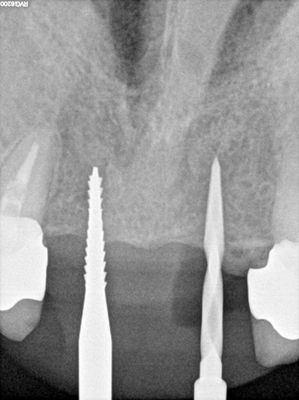

NSankhyan - immediate 13, impls 1121 and 25 with grafting

13 exo, loss of labial plate, implant placed buccal region grafted with sticky bone and collagen membrane soaked in prf fluid. 11/21 limited Labial-palatal width of bone, ridge split to 5mm, osteotomies prepared to about 2mm, remainder with densah drills, implants placed with ample bone, buccal grafted with same sticky bone. densah drills used for apical portion of 25 implant, soft bone, implant placed